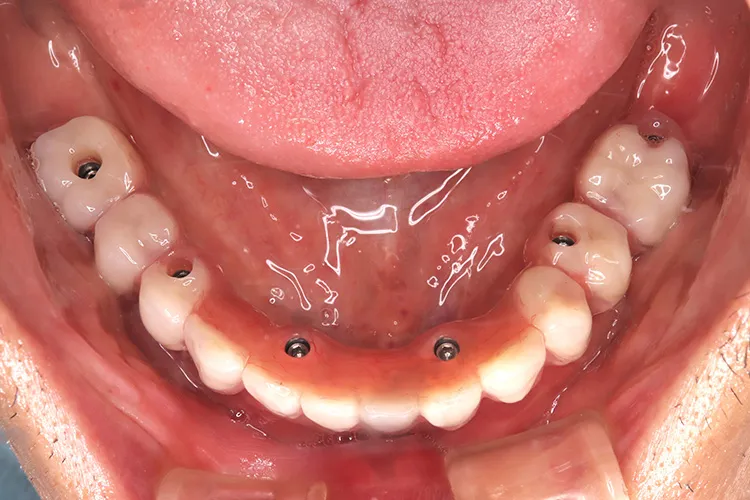

ボーンアンカードブリッジの下顎症例です。同じようにインプラント6本で上部構造を支えることができます。